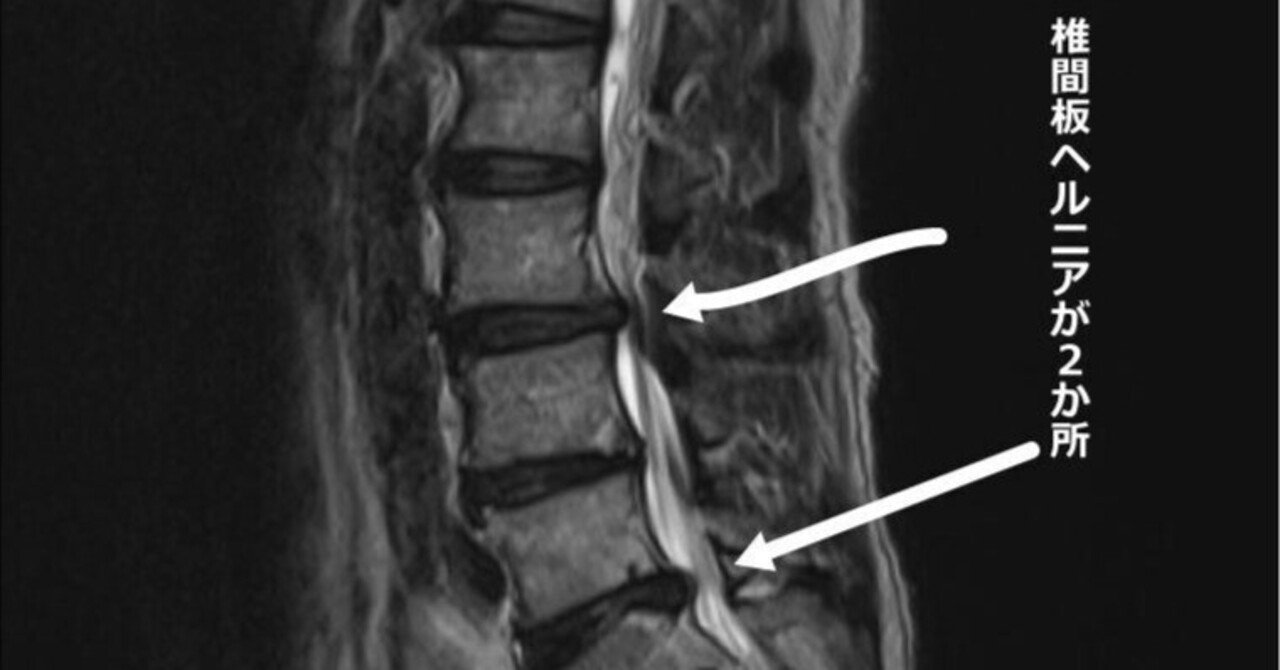

世の中には結構な数の腰痛持ちの方がいらっしゃるんだなと、出て来る腰痛ベルト、補正ベルト、矯正ベルト等の数の多さで実感するラグマスターです。かく言う私も腰椎椎間板ヘルニアでお世話になった一人です。その時の手術の記事はこちらから▼